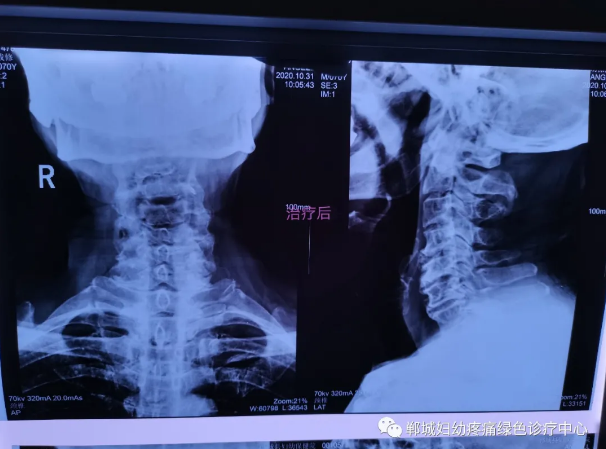

治療前李老師頸椎X線檢查影像

1個(gè)療程治療后頸椎X線檢查對(duì)比